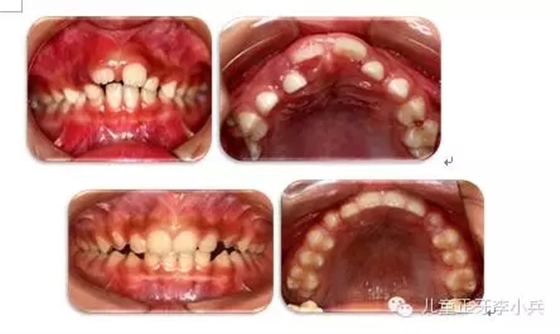

3. 牙槽骨早期塑形矯治:良好的咬合必須是上下頜骨大小位置正常、上下牙大小排列正常,以及上下牙弓的大小與形態(tài)協(xié)調(diào)。臨床功能矯形可調(diào)整上下頜骨大小與位置的不調(diào);臨床正畸治療可矯治牙齒排列異常。而上下牙槽骨的大小形態(tài)不協(xié)調(diào)的早期矯治就是牙槽骨的早期塑形。牙槽骨的發(fā)育包含牙槽骨長、寬、高三項的發(fā)育,常見的牙槽骨發(fā)育異常是寬度的不足,形成功能性下頜后縮及牙列擁擠。早期的牙槽骨括弓能打開腭中縫,擴大牙弓寬度,增加牙弓周徑,避免功能性II類及擁擠的發(fā)生。(圖4,早期牙槽骨塑形矯治)

圖4 上頜牙弓狹窄,牙槽骨擴弓塑形促進上下牙弓正常發(fā)育;